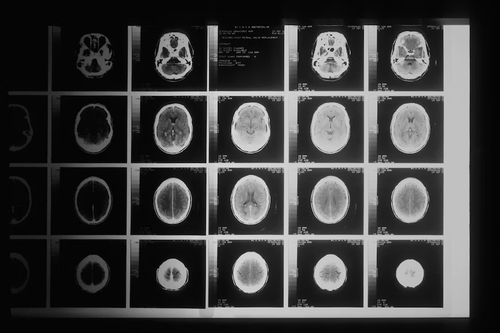

Заглавно изображение: Магнитно-резонансна томография. Източник: Unsplash